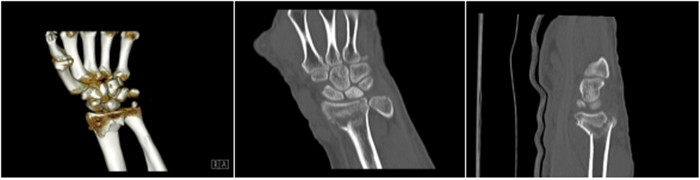

明峰CT搭載了領(lǐng)先的硬件技術(shù)平臺及系統(tǒng),強(qiáng)大的掃描能力可滿足臨床的各種要求,呈現(xiàn)更極致的細(xì)節(jié),為各臨床科室提供高品質(zhì)的圖像。薄層掃描,消除部分容積效應(yīng),提高各向同性。配合高分辨率算法,有助于細(xì)微結(jié)構(gòu)和形態(tài)學(xué)顯示。